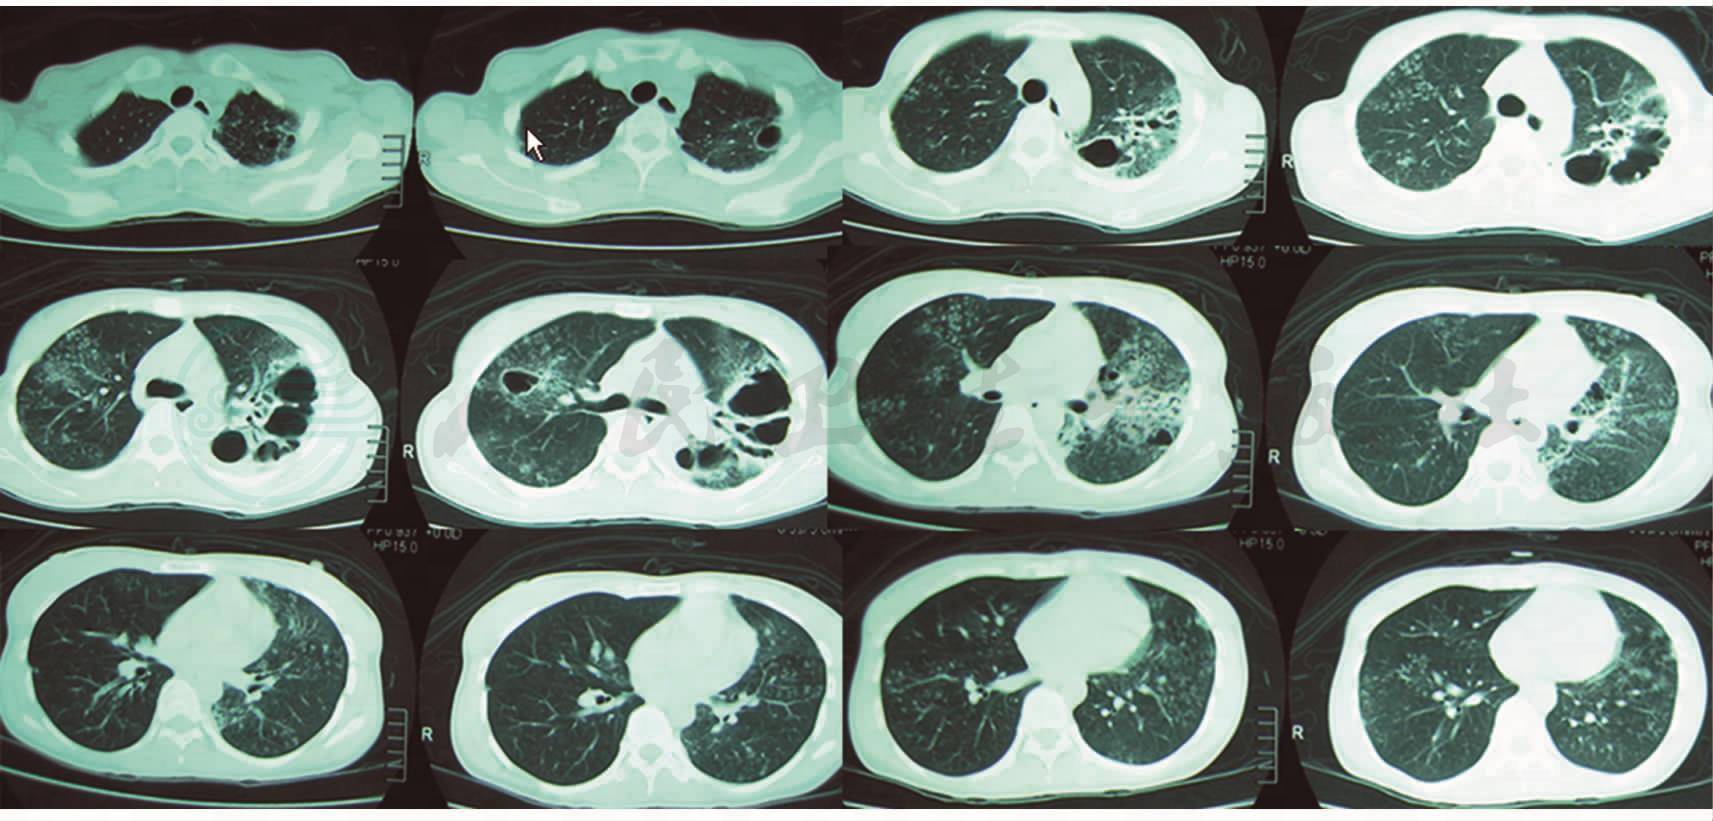

图3 胸部CT(2008年9月17日):双肺弥漫性磨玻璃样病变

图4 抗结核治疗2个月后胸部CT复查(2008年11月29日):病变范围明显增加

患者于2008年6月起无明显诱因出现咽痛,开始为说话时咽部不适感,于当地医院就诊,胸片检查提示肺部炎症(图1),予抗感染治疗6天后复查胸片(图2)未见好转,反见加重。拟诊为“肺结核”,于2008年7月2日开始给予利福喷汀、乙胺丁醇、帕司烟肼三联抗结核治疗2个月,其间曾因出现肝功能损害,停用抗结核药并护肝治疗1周后继续抗结核治疗。治疗后,患者咽痛症状无改善,呈进行性加重,严重时吞咽疼痛影响进食,先后于2008年8月、2008年9月两次复查胸片未见好转,行胸部CT检查示双肺弥漫性磨玻璃样病变(图3),又开始给予利福喷汀、乙胺丁醇、链霉素、左氧氟沙星四联抗结核治疗。治疗2个月后(2008年11月),患者症状无改善,复查胸部CT提示病变范围明显增加(图4)。遂于2008年12月转至上级医院就诊,行咽组织活检,病理见多核巨细胞、上皮样细胞构成的结核样结节,未见典型干酪样坏死,考虑增殖型结核可能性大;继续抗结核治疗,同时超声雾化吸入“异烟肼、链霉素”治疗2周。此后(2009年1月)患者开始出现咳嗽,多见于早晨,开始为阵发性单声咳,后咳嗽加剧,为持续性,伴咳白色泡沫痰,偶痰中见血丝,伴轻度活动后气促。遂到某结核病专科医院就诊,复查胸片考虑双侧上、中、下肺野结核并双上肺空洞(图5)。继续抗结核治疗,1个月后(2009年2月)复查胸片提示病灶较前有吸收,空洞缩小(图6)。但患者症状无好转,2个月后复查胸片提示“双肺病灶增多,左上肺空洞增大”(图7)。于该院住院,纤维支气管镜活检病理见由上皮样细胞和朗格汉斯细胞组成的结核样结节,未见干酪样坏死。入院约1周后胸部CT检查提示双肺病变较前有所减少(图8)。2009年5月患者出院,停用抗结核治疗。抗结核治疗期间,患者多次行痰涂片检查未见抗酸杆菌,PPD皮试阴性。患者仍咳嗽、咳痰,服用中药治疗,咳嗽、咳痰稍改善。2009年9月,患者开始出现发热,多于早晨出现,体温最高39℃,下午可自行下降。2009年9月底,于本院门诊行胸部CT示双肺弥漫性片状磨玻璃样、粟粒状阴影,较外院CT片病变进展(图9),考虑感染性病变而收入院进一步治疗。患病期间,患者无胸闷、呼吸困难,无午后低热、盗汗,无关节疼痛、口腔溃疡等。食欲缺乏,精神欠佳,体重下降约5kg。既往体健,个人史、月经婚育史、家族史无特殊。